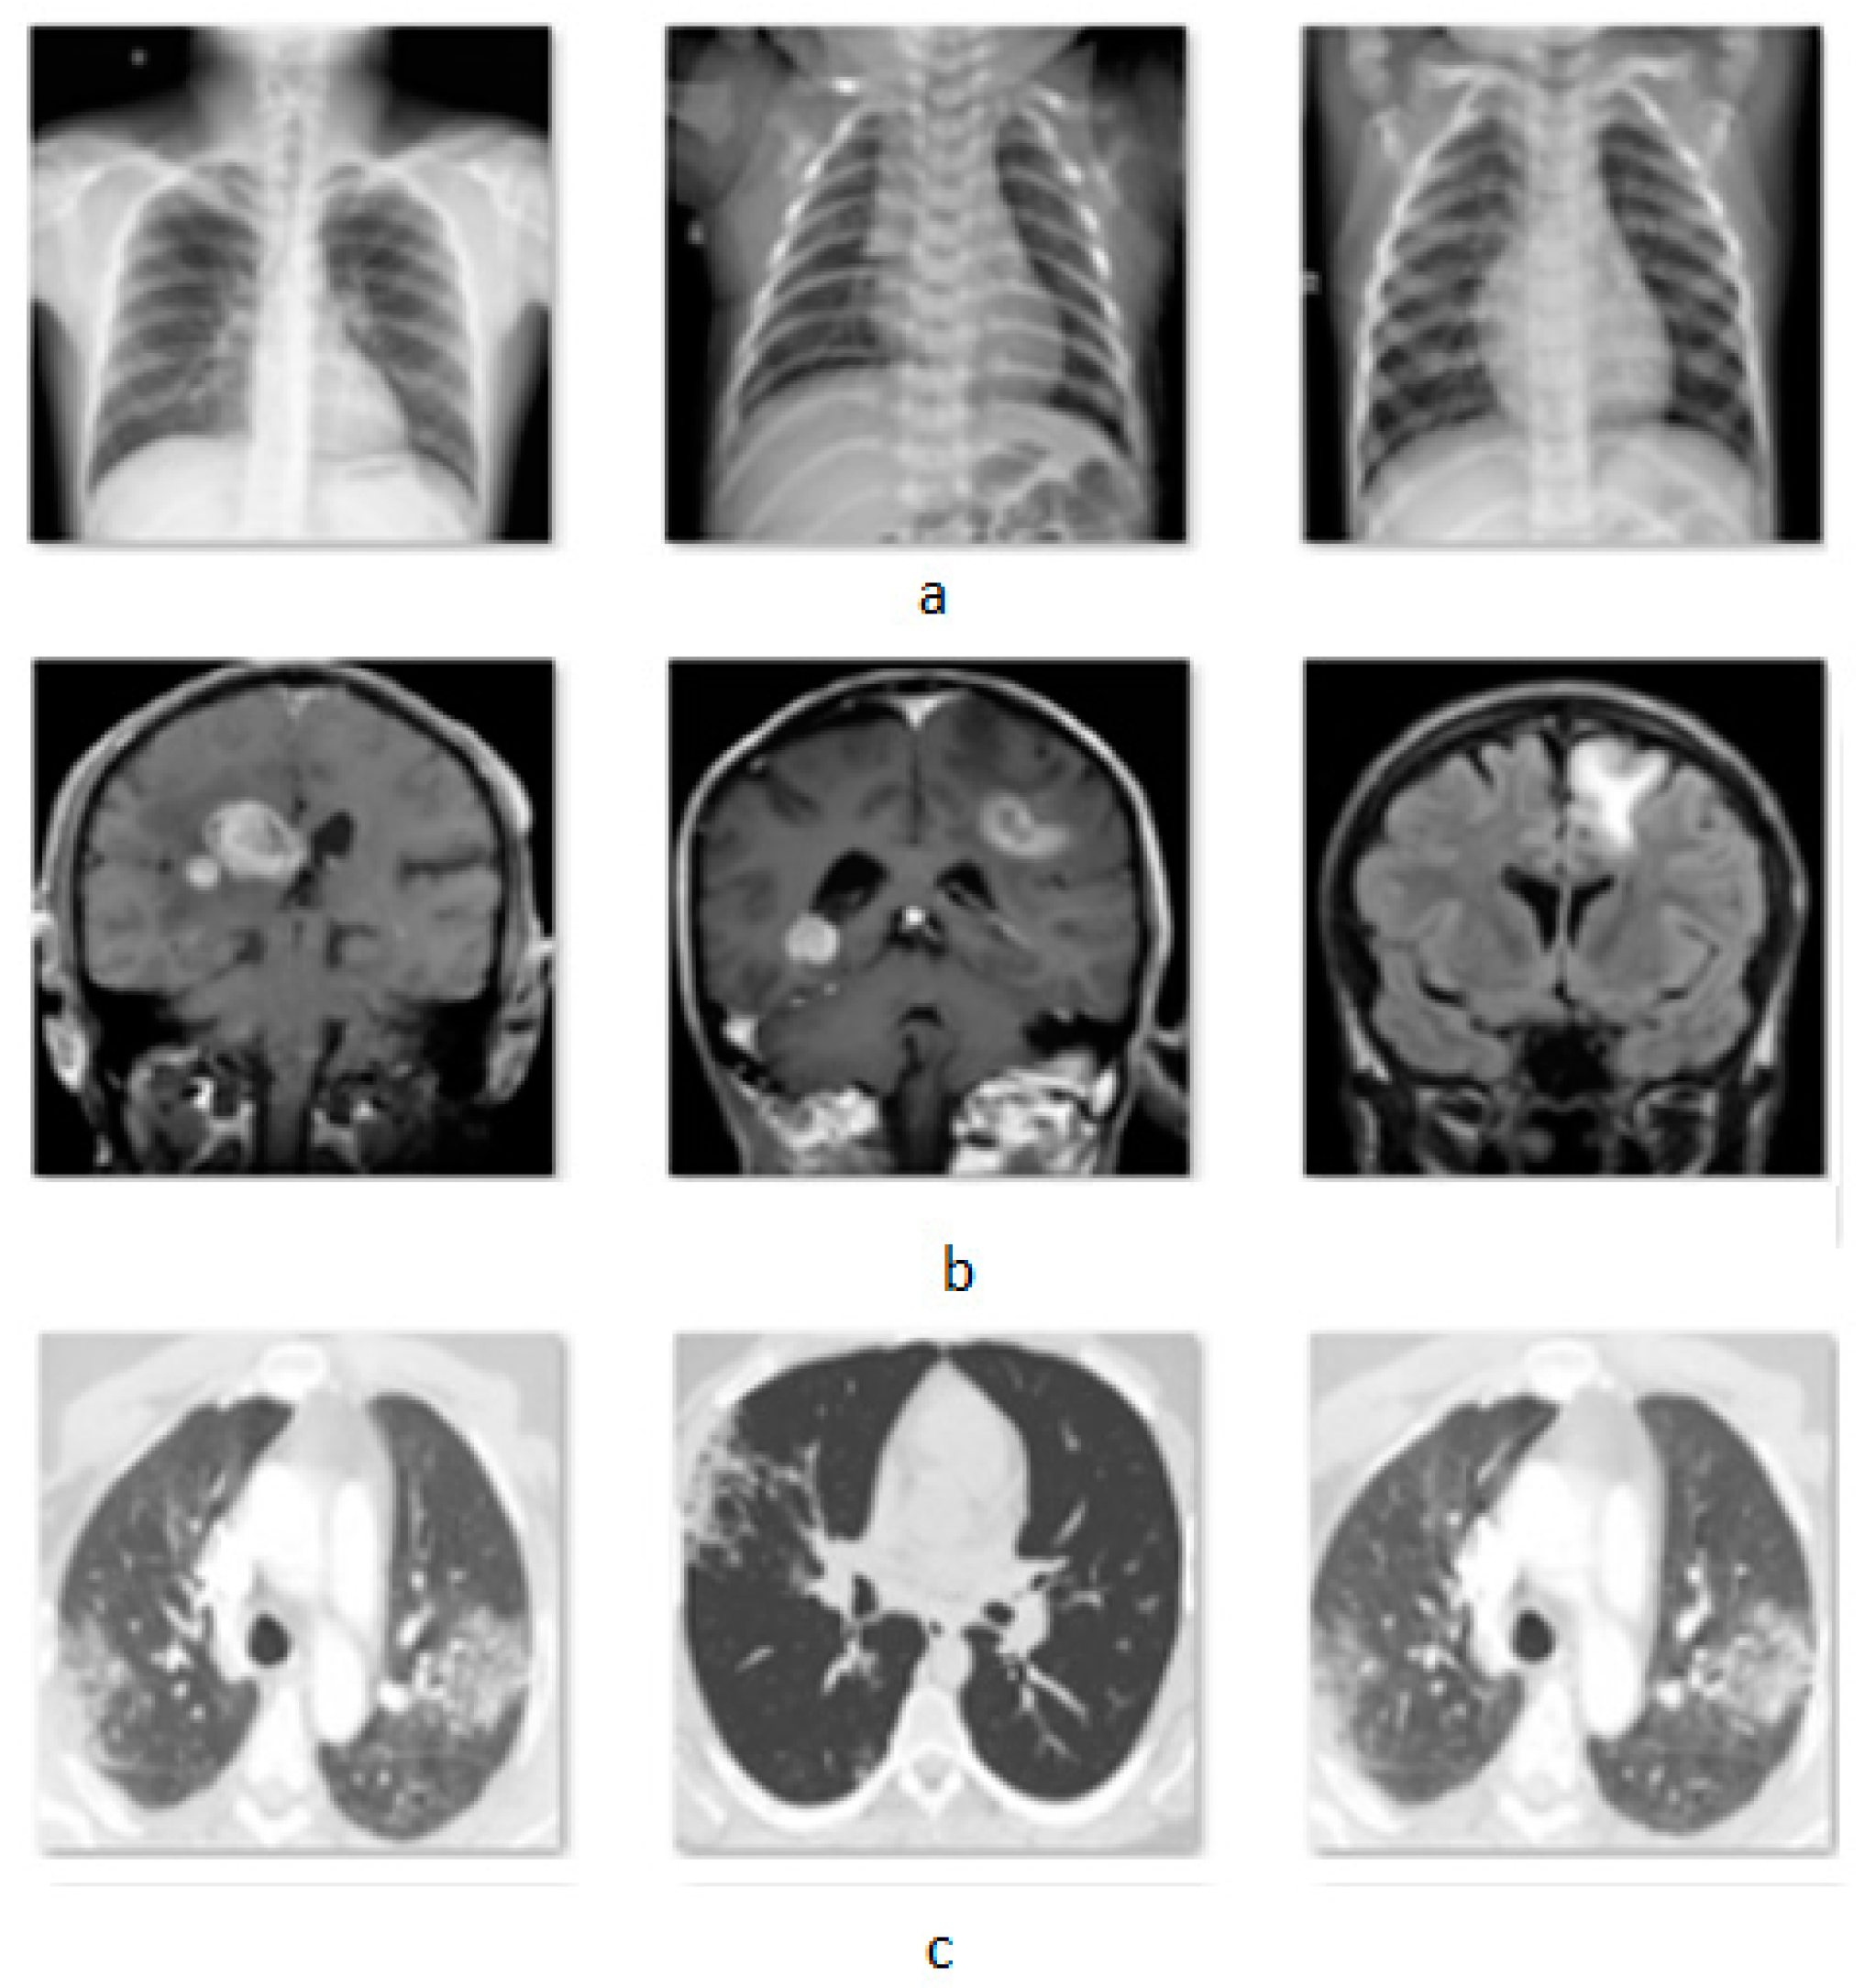

The attack was applied in classification problems in three different modalities. The first dataset [38] is an X-ray set from the lungs that classifies the images into three categories, normal, pneumonia, and COVID-19, containing 3840 images. The second dataset [39] consists of brain MRIs of four tumor categories with 3264 total images and the last dataset [40] is a binary classification of CT-Scans for COVID-19 and non-COVID-19 lungs, providing 2481 images. In Figure 2 is presented a sample of the used datasets.

Figure 2.

Images from three datasets, (a) X-rays, (b) MRIs, and (c) CT-Scans.